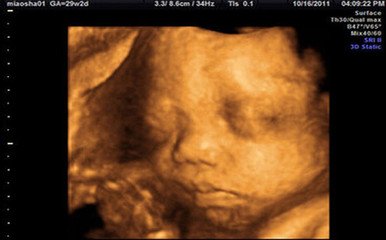

23周的胎儿现在身长大约19厘米,体重400克左右,在这个时候的胎儿 听力基本形成,他(她)已经能够辨认你的说话声音,心跳声音,肠胃蠕动发出的声音。宝宝肺中的 血管形成, 呼吸系统正在快速的建立。宝宝在这时候还会不断的吞咽,但是他(她)还不能排便,直到出生后他(她)才会自己独立完成这件事情。